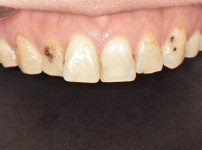

상악전치부 심미보철

최OO님/치료기간:2주/상악전치...